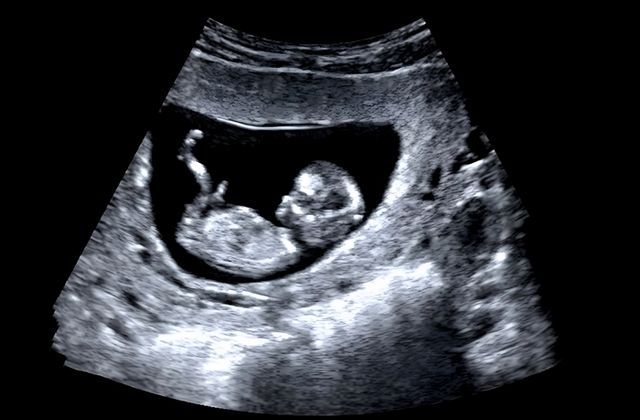

기사의 이해를 돕기 위한 사진 / Barou abdennaser-shutterstock.com